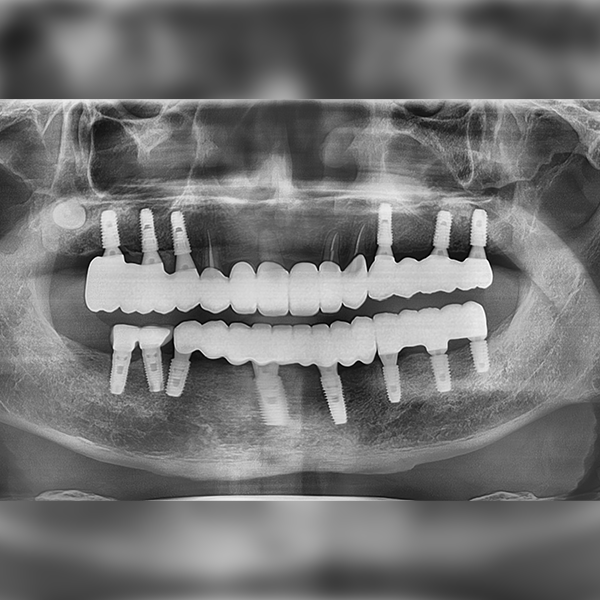

上顎/前牙部位 / 4顆以上 / 補骨|舒眠|高血壓

案例155 60多歲 鄭*澤 2022-04-23 / 2019-11-28